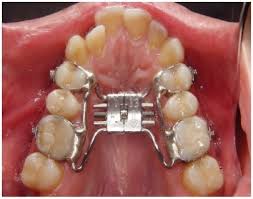

Disjuntor mais utilizado em disjunções rápidas da maxila. O HYRAX é um aparelho expansor preso aos dentes pela parte interna junto ao céu da boca. Quanto ao hyrax espero também não ter que ativa-lo mais.

Aparelho dentário adicione um dos valores acima conforme o aparelho escolhido. Ambos são construídos com o uso de fios muito rígidos e soldados ao parafuso disjuntor palatino. 71 reais con 35 centavos R 71.

Ele é usado em casos que o osso maxilar é muito estreito.